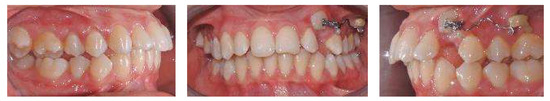

An 18-year-old female patient was referred, complaining of unpleasant smile. She presented good general health and no systemic or congenital diseases. From a frontal view, the patient presented a well-proportioned three-thirds of her face and no evidence of asymmetry. From the lateral view, the profile appeared convex with well-represented nasolabial angle, labiomental sulcus, and lip competence. Intraorally, the patient showed a Class II malocclusion with the molar Class I relationship, edge to edge canine relationship on both sides, increased overjet, overbite, and the retention of the 63. Panoramic, lateral headfilm, and dental cast records were taken (Figure 11).

Figure 11.

An 18-year-old female with dentoskeletal Class II with impacted upper left canine before treatment.